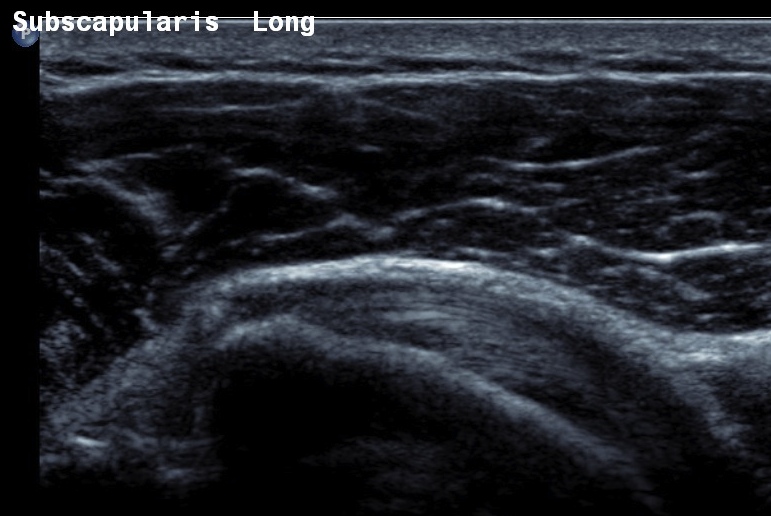

Ultrasound

Normal

- systematic review of US rotator cuff tears

- US more accurate for supraspinatus and biceps than subscapularis

- US more accurate for full thickness tears than partial thickness tears